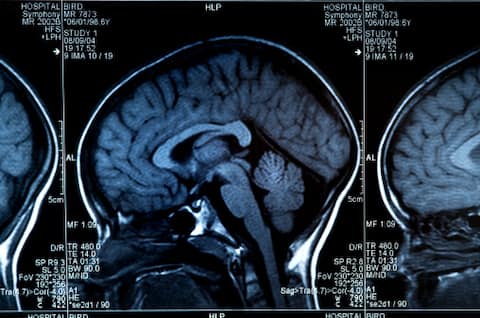

শুধু তাই নয়, এমআরআই স্ক্যানও করেছিলেন গবেষকরা। দেখা যায় মস্তিষ্কের সামনের অংশের কর্টেক্সে বেশ কিছু কার্যকারীতা দেখা যায়। যেখানে কতটা ক্লান্তি মানুষের কাজ চালিয়ে যাওয়ার প্রেরণাকে প্রভাবিত করছে তা বোঝা যায়।